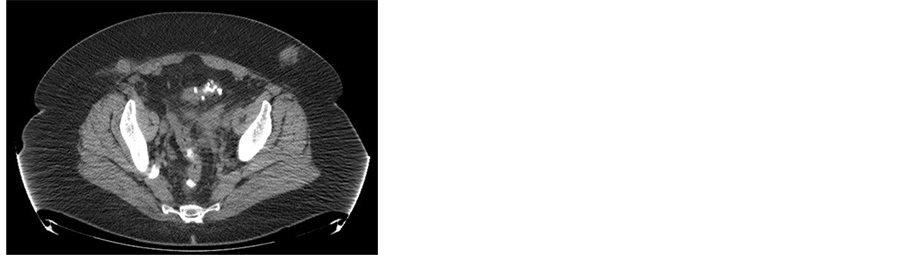

(a)(b)(c)(d)

Figure 5. (a) Incarcerated hernia; (b)-(d) CT scan of the abdomen shows metastases in the subcutaneous tissue in the sites of the laparoscopic ports.